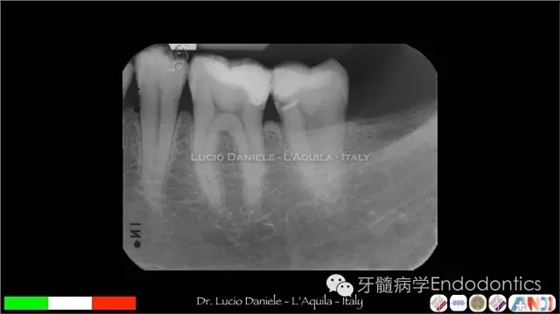

圖1. MTA直接蓋髓

圖5.隨訪2年、4年、10年